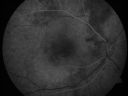

Central Serous Retinopathy705 viewsRed Free photo